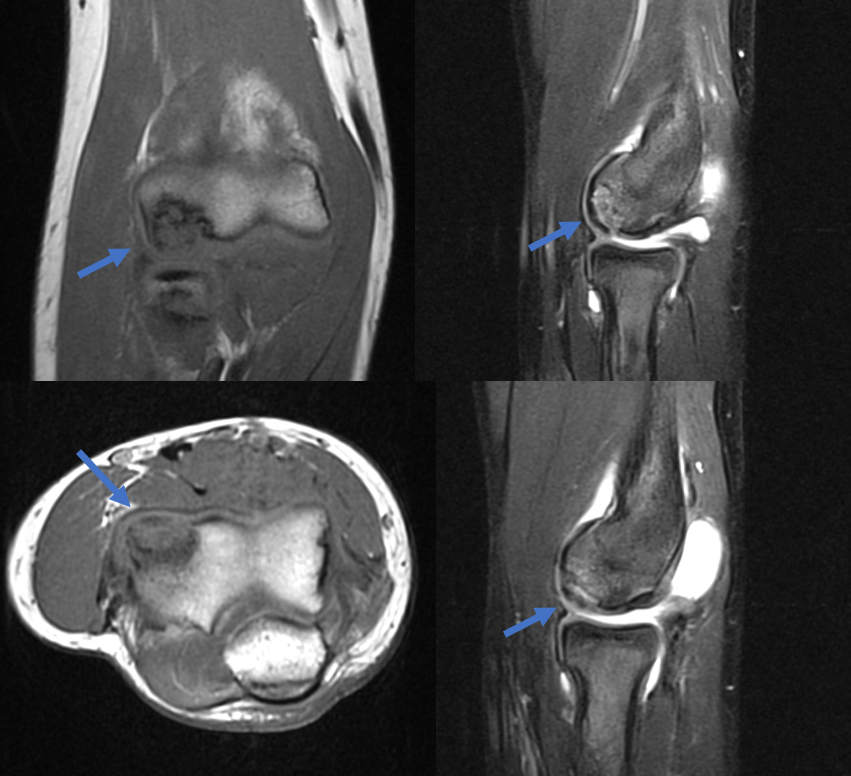

- MRI can help define stability of Grade II lesions

- Irregular contour or discontinuity of articular cartilage on MRI suggests unstable lesions

MRI demonstrates an unstable fragmented lesion within the capitellum